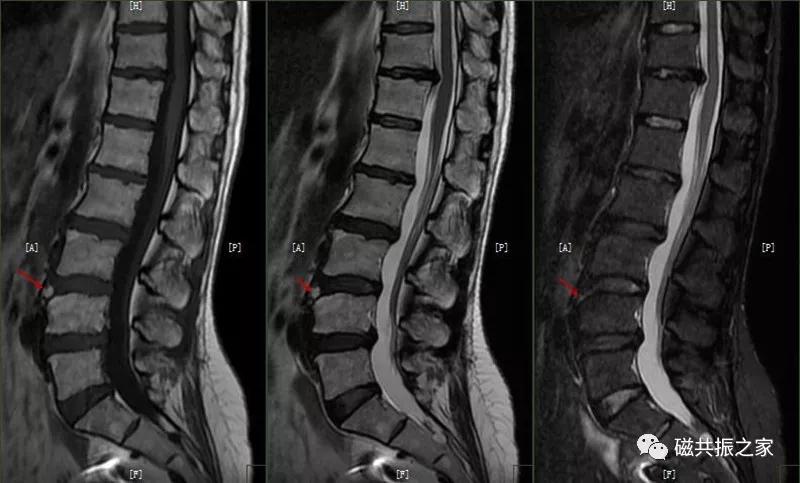

8.椎体骨折

椎体压缩性骨折常成前窄后宽的楔形改变,新鲜骨折(红箭头)常在T1WI呈低信号(出血时可呈高信号),T2WI呈低、中信号,在脂肪抑制的T2WI上呈高信号。椎体陈旧性骨折(白箭头)信号类似于正常椎体信号。如需了解脊柱骨折分型请查阅脊柱骨折的分型。